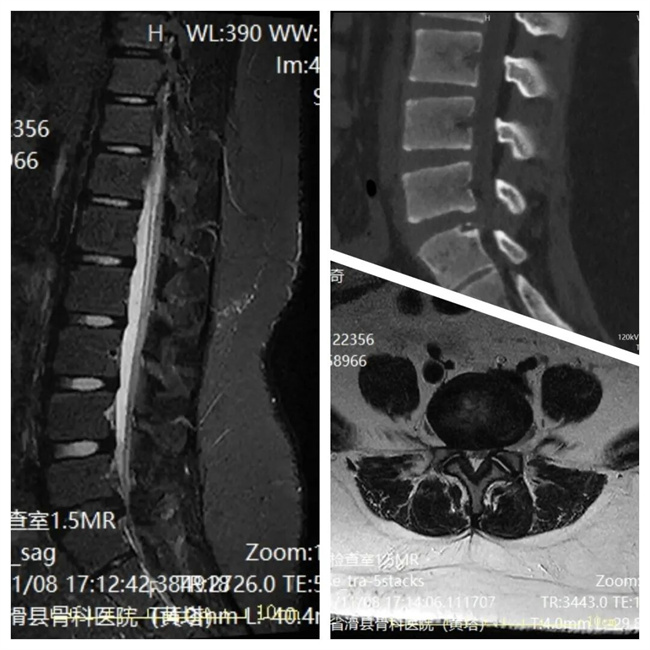

一、患者乔某某,女,11岁,患者腰部及右下肢疼痛、麻木半年余,活动受限。为求进一步治疗,来到我院请专家会诊,通过各位专家会诊查体、查看影像资料并细致认真的分析后,建议:微创手术治疗(内镜下髓核摘除)。